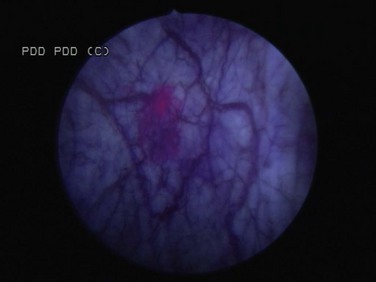

Photoactive porphyrins accumulate preferentially in neoplastic tissue. Under blue light they emit red fluorescence, which can help in the diagnosis of indiscernible malignant lesions. Hematoporphyrin derivatives must be administered systemically and can cause lengthy, residual cutaneous photosensitization. Intravesical application of 5-aminolevulinic acid (5-ALA), a precursor of photoactive porphyrin, avoids residual systemic photosensitization and has improved the detection of bladder tumors. Modifications of 5-ALA may allow deeper tissue penetration and improved accumulation in neoplastic cells (Lange et al, 1999). A more lipophilic ester, hexaminolevulinate (HAL), is the most studied agent.

When using this technology, both small papillary tumors and almost one-third more cases of CIS overlooked by cystoscopy are identified (Jichlinski et al, 2003; Schmidbauer et al, 2004; Fradet et al, 2007). Of all tumors, 96% were detected with HAL imaging compared with 77% using standard cystoscopy. Detection was improved for dysplasia (93% vs. 48%), CIS (95% vs. 68%), and papillary tumors (96% vs. 85%) (Jocham et al, 2005). The clinical impact of improved tumor detection seems intuitive, and prospective evidence shows that this decreases recurrence rates in patients who undergo HAL fluorescence cystoscopy compared with controls (Filbeck et al, 2003; Denzinger et al, 2007).

Intravesical HAL for use with fluorescence cystoscopy received approval for use in Europe in 2004. A multinational study to determine the actual impact on recurrence rates before approval in North America showed similar findings (unpublished data) (Figs. 81-6 and 81-7).

Figure 81–6 White light microscopy reveals normal appearing mucosa.

(Courtesy of H. Barton Grossman, MD.)

Figure 81–7 Blue light microscopy reveals accumulation of hexaminolevulinate in an area proven subsequently to contain a small focus of carcinoma in situ.